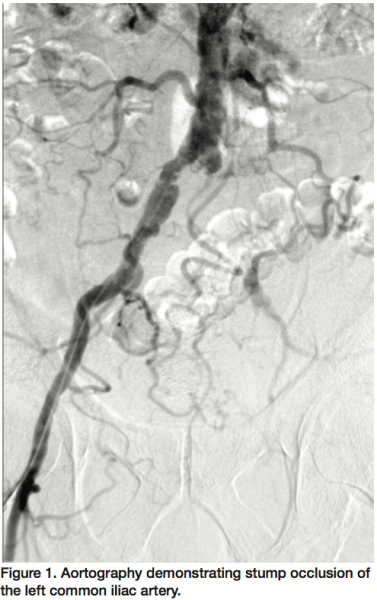

The procedure was performed in the surgical suite with a portable C-arm fluoroscopic imaging unit with the patient under regional anesthesia. A 7 Fr 90 cm Shuttle sheath (Cook Medical) was used to cannulate the left CIA via high right brachial artery access and the lesion crossed using a Frontrunner® XP CTO catheter (Cordis). Meanwhile, an open surgical common femoral endarterectomy (duplex ultrasound prior to the procedure confirmed a short segment of patent but diseased CFA with retrograde flow from the collaterals) and profunda femoris profundoplasty was performed to allow inflow into the left foot via the profunda femoris and collaterals to the popliteal artery. A Micro Guide Catheter XP (Cordis) was advanced over the Frontrunner catheter; a 260 cm 0.035 inch straight tip stiff Aquatrack® wire (Cordis) was directed through the Micro Guide catheter; the wire exteriorized through the common femoral endarterectomy site; and the femoral artery clamped over the wire at the inguinal ligament (Figure 2). Balloon angioplasty was performed in the left CIA and left external iliac arteries (EIA) using a 6 x 100 mm Powerflex balloon (Cordis) with multiple inflations at a maximum pressure of 8 atmospheres. A 10 x 38 mm iCAST™ covered stent (Atrium Medical) was deployed in the left CIA with one inflation at 10 atmospheres followed by post-dilatation using a 9 x 40 mm Powerflex balloon (Cordis) with 2 inflations at a maximum pressure of 12 atmospheres. An adjacent self-expanding SMART® nitinol stent (Cordis) was placed overlapping the CIA stent and extending to the inguinal ligament followed by post-dilatation using a 9 x 40 mm Powerflex balloon (Cordis) with 5 inflations at a maximum pressure of 10 atmospheres. The distal end of the exteriorized wire was directed into the profunda femoris artery and the femoral artery unclamped, the endarterectomy perfected, and the surgical site irrigated and closed in layers. Subsequent angiography confirmed patent left CIA and EIA (Figure 3) and good single vessel runoff into the foot. The patient was monitored for 36 hours and discharged home on postoperative day 2 with minimal restrictions and wound care instructions. Patient was seen at 1 month follow-up with significant improvement in symptoms and patent common femoral and profunda femoris arteries by arterial duplex ultrasonography with an improved ankle-brachial index of 0.79.